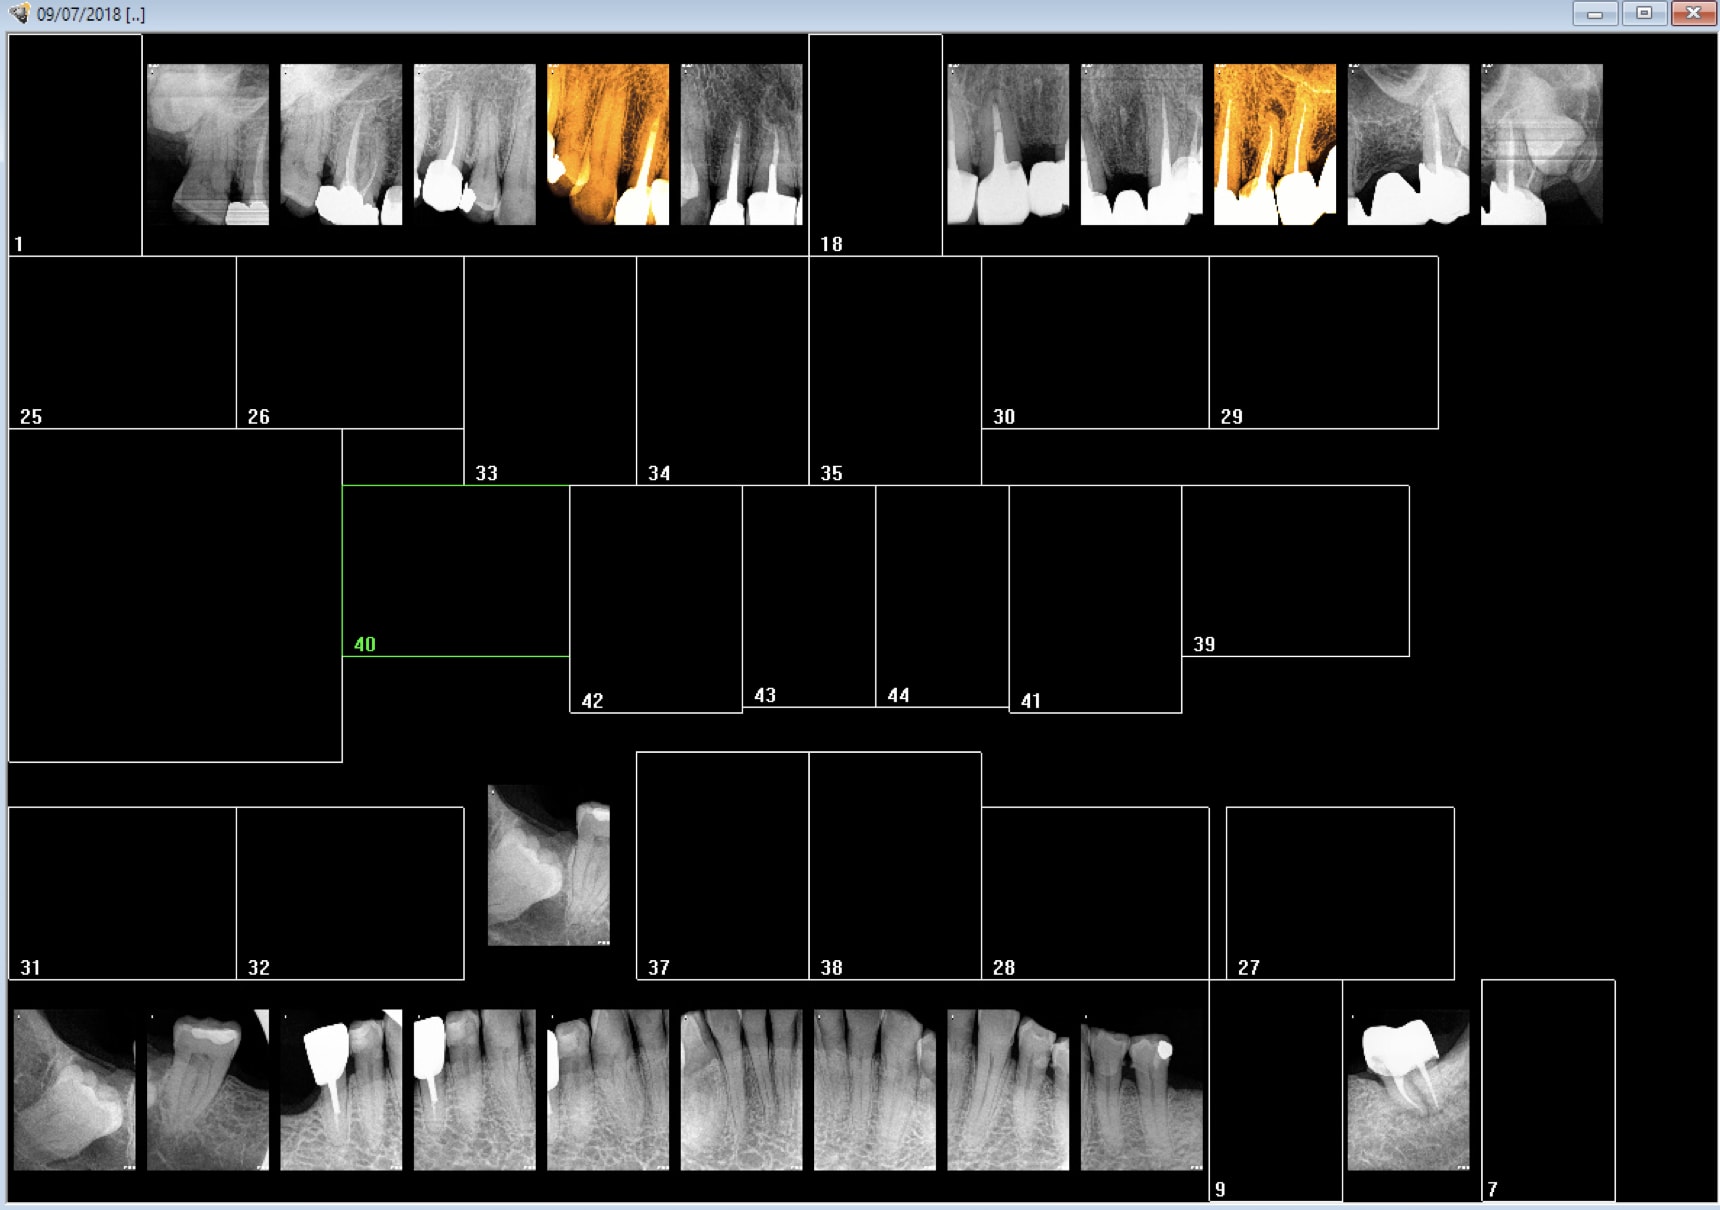

> Le choix c'est l'indication.

> Y'a aucune justification à réaliser des bilans long cône systématiques.

> Pano et long cone n'ayant pas les mêmes finalités, les opposer n'a pas grand

> sens.

> Tu vas pas faire de bilan d'évolution des 8 avec des retro. Tu vas pas faire un

> bilan paro avec une pano.

Pas de bilan d'évolution des 8 avec retro . Mmmmm ? Pas de bilan TIB systématique seulement des bilans "personnalisés"si antécédents de soins intensifs ou maladie dentaire diffuse. -)))